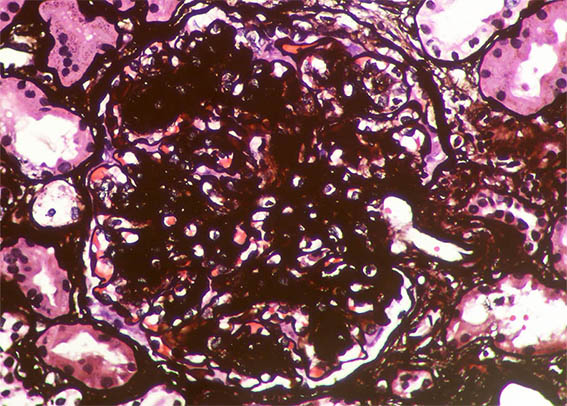

Figure 8. Methenamine-silver stain, X400.

Figure 10. Methenamine-silver stain, X400. Note the nodule on the upper right, surrounded by basement membrane (possibly microaneurysm with organizing thrombus).